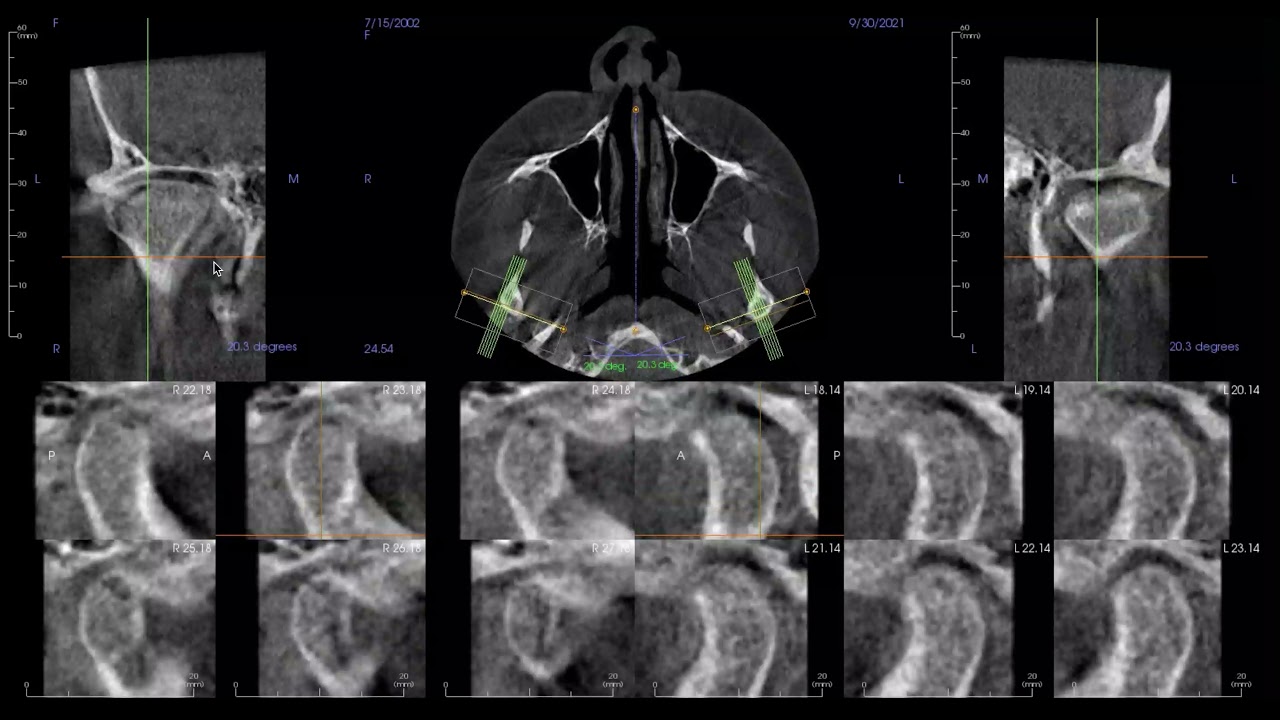

ВНЧС на КТ с конусным пучком

7462 6 лет назад 6:02